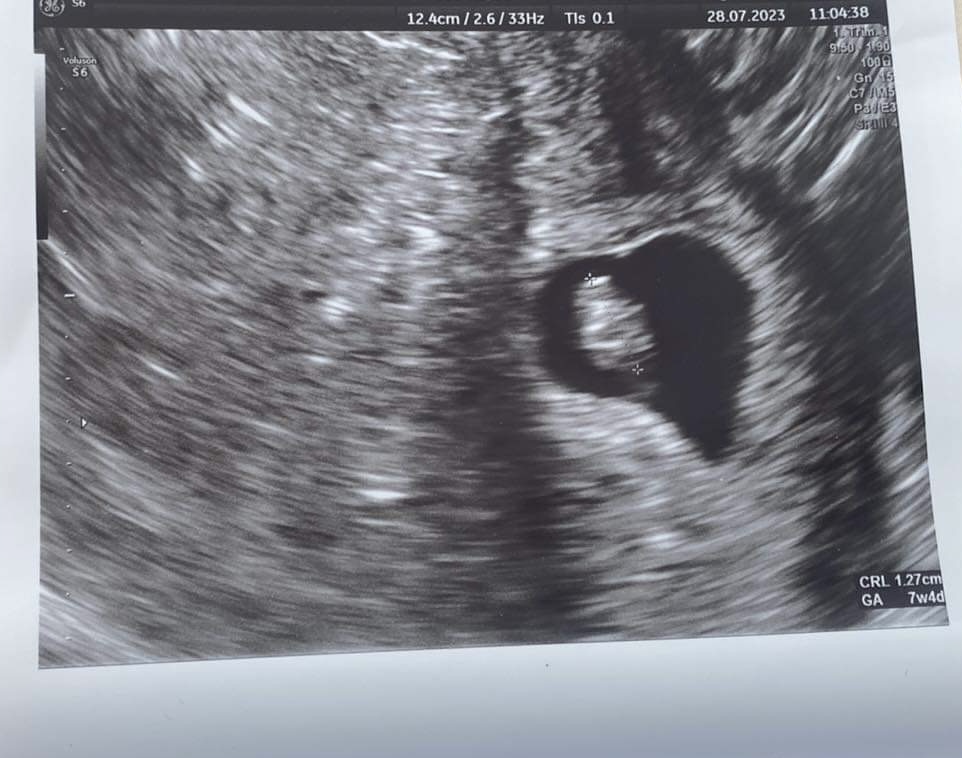

Ultrazvuk- je tam aj druhé bábo?

Sice mas mily obrazok, ze to vytvorilo zrovna nahodne tvar srdca (normalne by som si to dala prefotit na fotopapier a tu cast zaramovala), ale ine tam nevidim. Ten tien hore je len tien niecoho ineho a v blizkosti toho druheho dlheho tiena prebiehajuceho zhora nadol to vytvara zdanie druhej dutinky.

Kazdopadne, ak by mal doktor pocit, ze tam nieco dalsie je, urcite to podrobne pozrel na vysetreni.